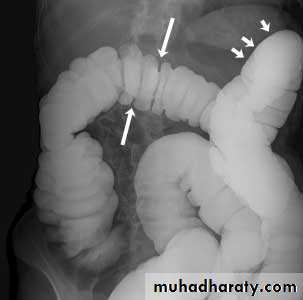

Ulcerative colitis (UC)is an inflammatory bowel disease which predominantly affects the colon, but also has extra intestinal manifestations.

Location

o Begins in rectum with retrograde progressiono Rectosigmoid involved 95%; continuous involvement of left colon

oTerminal ileum in 5-10% with backwash ileitis

Ulcerative colitis (UC)

X-Ray ManifestationsAcute inflammatory stage

o Spasm and irritability

o Fine mucosal granularity earliest finding on air-contrast BE

o Spiculated, serrated bowel margins from tiny, multiple ulcerations

o Collar button ulcers

o Thumb printing from edema of wall

o Pseudopolyps

o Widening of the pre-sacral space

Chronic stage

o Shortening of the colon-may be from spasm of longitudinal muscles or from irreversible fibrosis (lead-pipe colon)

o Loss of haustrations on left side of colon

Barium enema examination demonstrates loss of haustral folds in the entire descendingcolon with small ulcerations suggested. The colon has a "lead-pipe" appearance. The distribution and appearance are suggestive of ulcerative colitis.